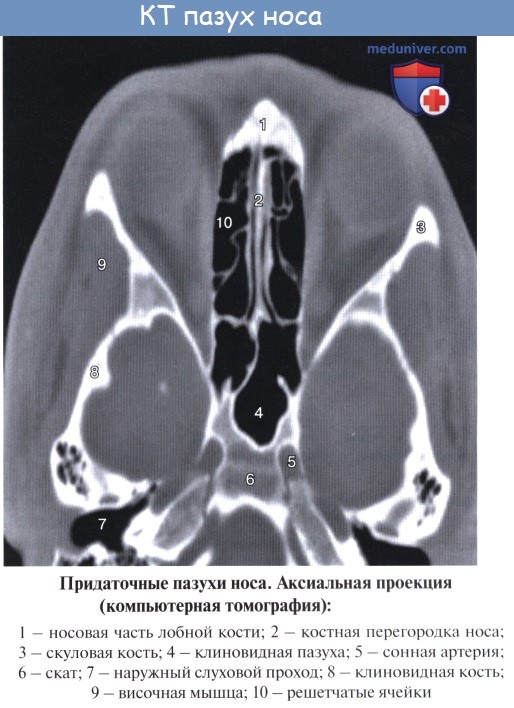

Околоносовые пазухи. Топография околоносовых пазух. Верхнечелюстная пазуха. Гайморова пазуха. Топография верхнечелюстной ( гайморова ) пазухи.

С каждой стороны к полости носа примыкают верхнечелюстная и лобная пазухи, решетчатый лабиринт и отчасти клиновидная пазуха.

Клиновидная пазуха, sinus sphenoidalis, расположена в теле клиновидной кости непосредственно позади решетчатого лабиринта над хоанами и сводом носоглотки. Сагиттально расположенной перегородкой пазуха делится на две в большинстве случаев неодинаковые по объему части. На передней, наиболее тонкой, стенке в каждой половине пазухи находится отверстие, apertura sinus sphenoidalis. Форма и размеры клиновидной пазухи сильно варьируют. Ее верхняя стенка обращена к передней и средней черепным ямкам.

Средний отдел верхней стенки клиновидной пазухи соответствует турецкому седлу с расположенным в его ямке гипофизом, а кпереди от них — перекресту зрительных нервов.

Снаружи по боковой стенке клиновидной пазухи проходят внутренняя сонная артерия и пещеристый венозный синус. Кроме того, по бокам пазухи проходят глазодвигательный, блоковый и отводящий нервы, прободающие наружную стенку пешеристого синуса, а также I ветвь тройничного нерва.

Нижняя стенка клиновидной пазухи образует свод полости носа.

Решетчатый лабиринт, labyrinthus ethmoidalis, состоит из 2—5 и больше различных по величине и форме решетчатых ячеек, cellulae ethmoidales, которые отграничены от передней черепной ямки орбитальной частью лобной кости и решетчатой костью, а от глазницы — глазничной пластинкой, lamina orbitalis. Сзади клетки решетчатого лабиринта иногда доходят до передней стенки клиновидной пазухи. Клиновидная пластинка решетчатого лабиринта, свободный край которой в полости носа является остовом средней раковины, делит воздухоносные клетки на передние и задние; передние клетки открываются в средний носовой ход, а задние — в верхний.